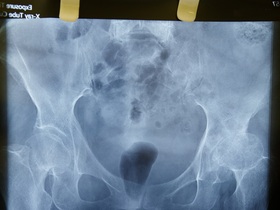

Металлоостеосинтез МОС голени ДО-ПОСЛЕ: